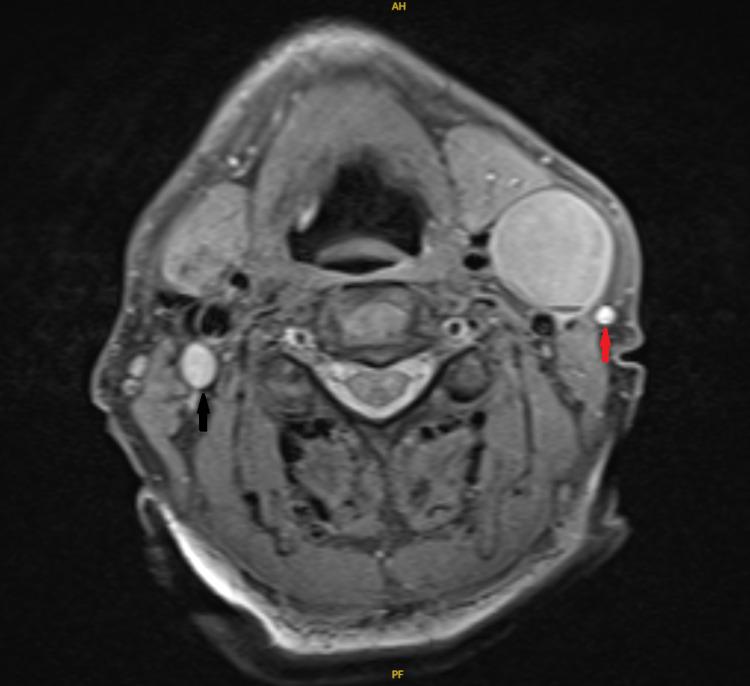

A comprehensive understanding of the anatomical variations of the internal jugular vein (IJV) is essential to prevent inadvertent injuries during neck procedures, particularly neck dissection. In addition, its relationship with the spinal accessory nerve in the upper part of the neck is relatively variable. IJV fenestration refers to bifurcation of the vein with reunion proximal to the subclavian vein, whereas IJV duplication refers to continued branching till joining the subclavian vein separately. We report a case of a fenestrated IJV identified intraoperatively with the spinal accessory nerve passing laterally to both divisions.

全面了解颈内静脉(IJV)的解剖变异对于预防颈部手术(尤其是颈部清扫术)期间的意外损伤至关重要。此外,它在颈部上部与副神经的关系相对多变。颈内静脉开窗是指静脉分叉后在锁骨下静脉近端重新汇合,而颈内静脉重复是指持续分支直至分别汇入锁骨下静脉。我们报告了一例术中发现的开窗型颈内静脉病例,副神经从两个分支的外侧通过。